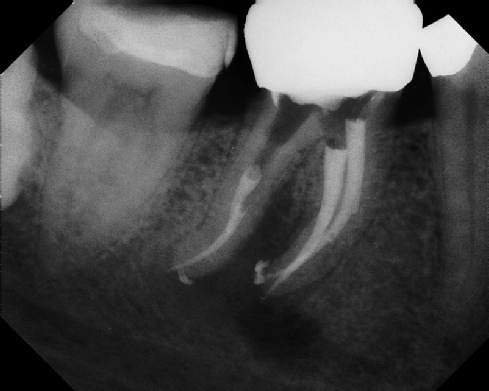

COMPLICATED ANATOMY LARGE LESIONS CALCIFIED CANALS PERFORATION / RESORPTION SEPARATED INSTRUMENTS SURGICAL CASES RETREATMENT / pOST REMOVAL OPEN APICES ACCESS THRU CROWNS Root Canal Case Portfolio

Pre-op Post-op 1 Post-op 2